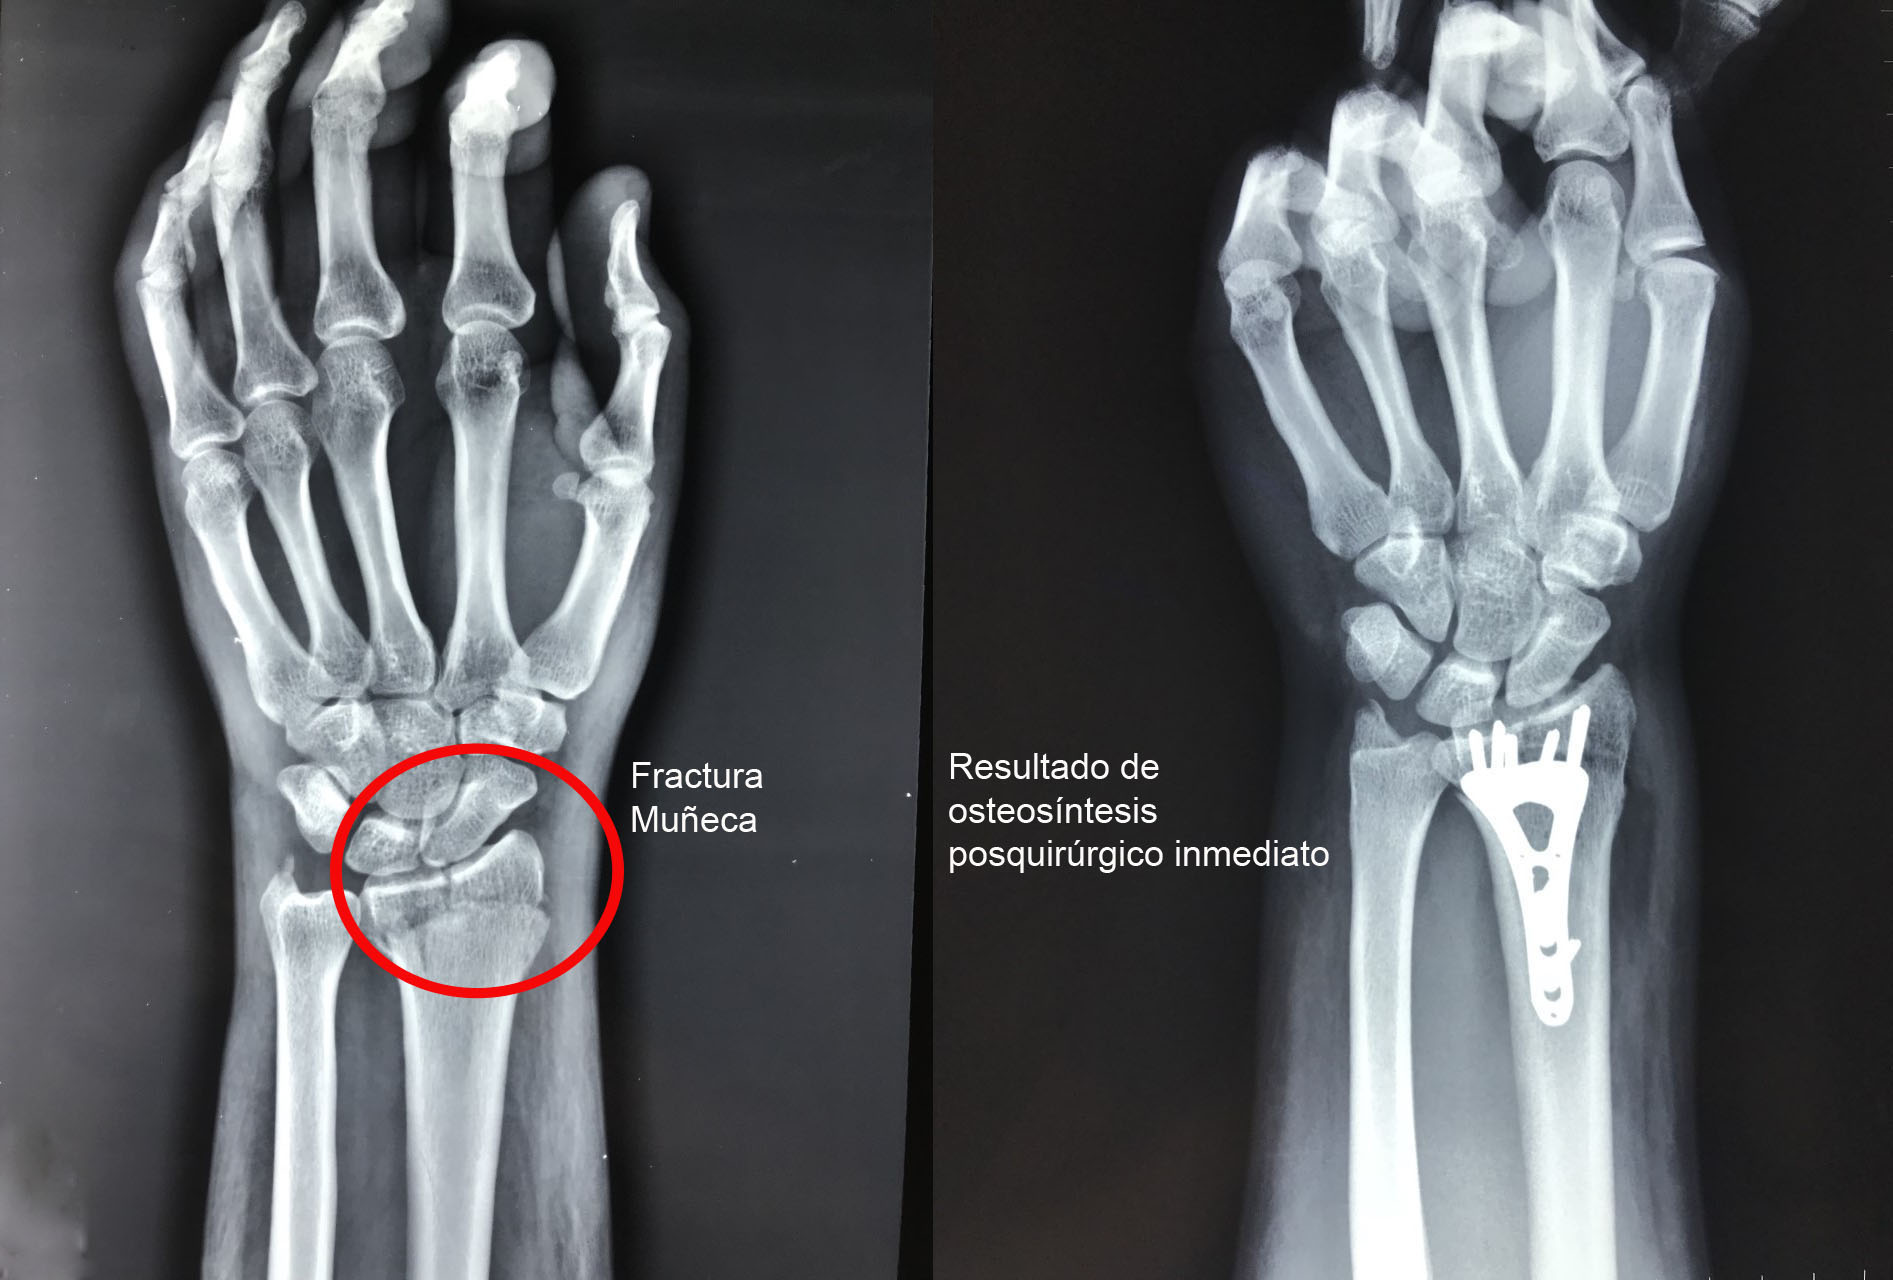

Una fractura ósea es la ruptura de un hueso, la cual puede presentarse por diversas causas y su tratamiento dependerá de la magnitud, sitio anatómico y de las enfermedades concomitantes. Algunas pueden manejarse de forma conservadora con solo inmovilización y hay otras que requieren de un tratamiento quirúrgico. A continuación, podrá ver algunos casos quirúrgicos, dando clic a la zona del cuerpo afectada.